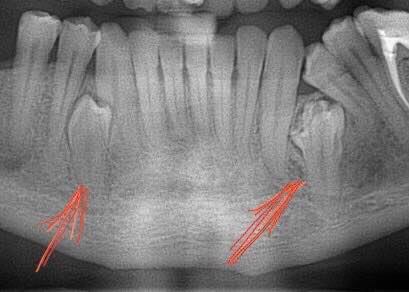

Чи є корені у молочних зубах?

Розповсюджений міф — що у молочних зубах немає коренів. Так думає більшість дорослих, коли бачать зуби, які випали у їхніх дітей. І дійсно, зуб, який випадає, вже не має коренів, вони повністю руйнуються і розсмоктуються на момент випадіння молочного зуба. Корені молочних зубів мають інше розташування ніж у постійних, і зверху над ними розміщені зачатки…